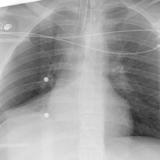

RLL Collapse 2 PA only

Date: 02/28/2004

Views: 3073